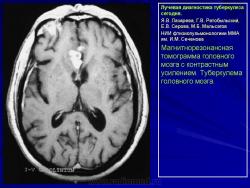

Лучевая диагностика туберкулеза сегодня

Я.В. Лазарева, Г.В. Ратобыльский, Е.В. Серова, М.Б. Мальсагов

НИИ фтизиопульмонологиии ММА им. И.М. Сеченова